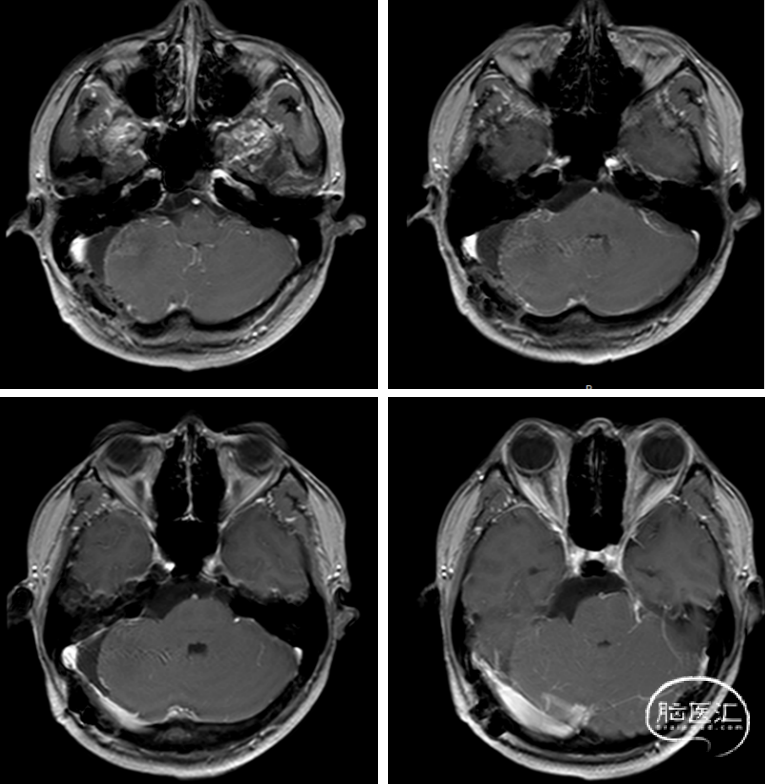

术后MRI